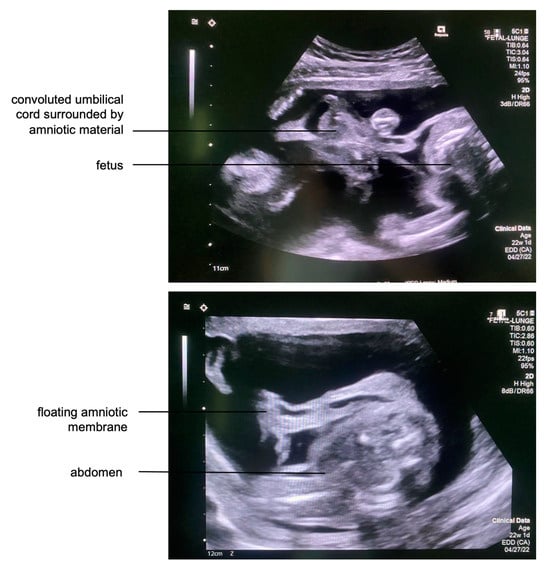

A 31-year-old pregnant woman (gravida 2, para 1) was referred to our center at 22 + 1 weeks of gestation after amniotic band syndrome had been detected in a previous routine ultrasound examination. All other screening examinations during her pregnancy were unremarkable. However, she did report vaginal bleeding in the first trimester. A maternal transabdominal fetal ultrasound revealed retroplacental hematoma, partial placental abruption, and subtotal chorioamniotic membrane separation, consistent with her history of vaginal bleeding in early pregnancy. Almost the entire amniotic membrane had separated from the chorion and floated freely in the amniotic fluid. The chorionic membrane seemed to be intact despite its separation from the amnion, as the amniotic fluid volume was normal and no vaginal fluid loss was seen. Multiple bands originating from the detached freely floating amniotic material and adhering to the fetus and its umbilical cord were observed (Figure 1).

Figure 1. Top: Transabdominal fetal ultrasound showing multiple strands of membranous material encircling and partially constricting the umbilical cord, indicative of a life-threatening state for the fetus. Bottom: Due to subtotal chorioamniotic membrane separation, the subtotally disrupted amniotic membrane floated freely next to the fetus.